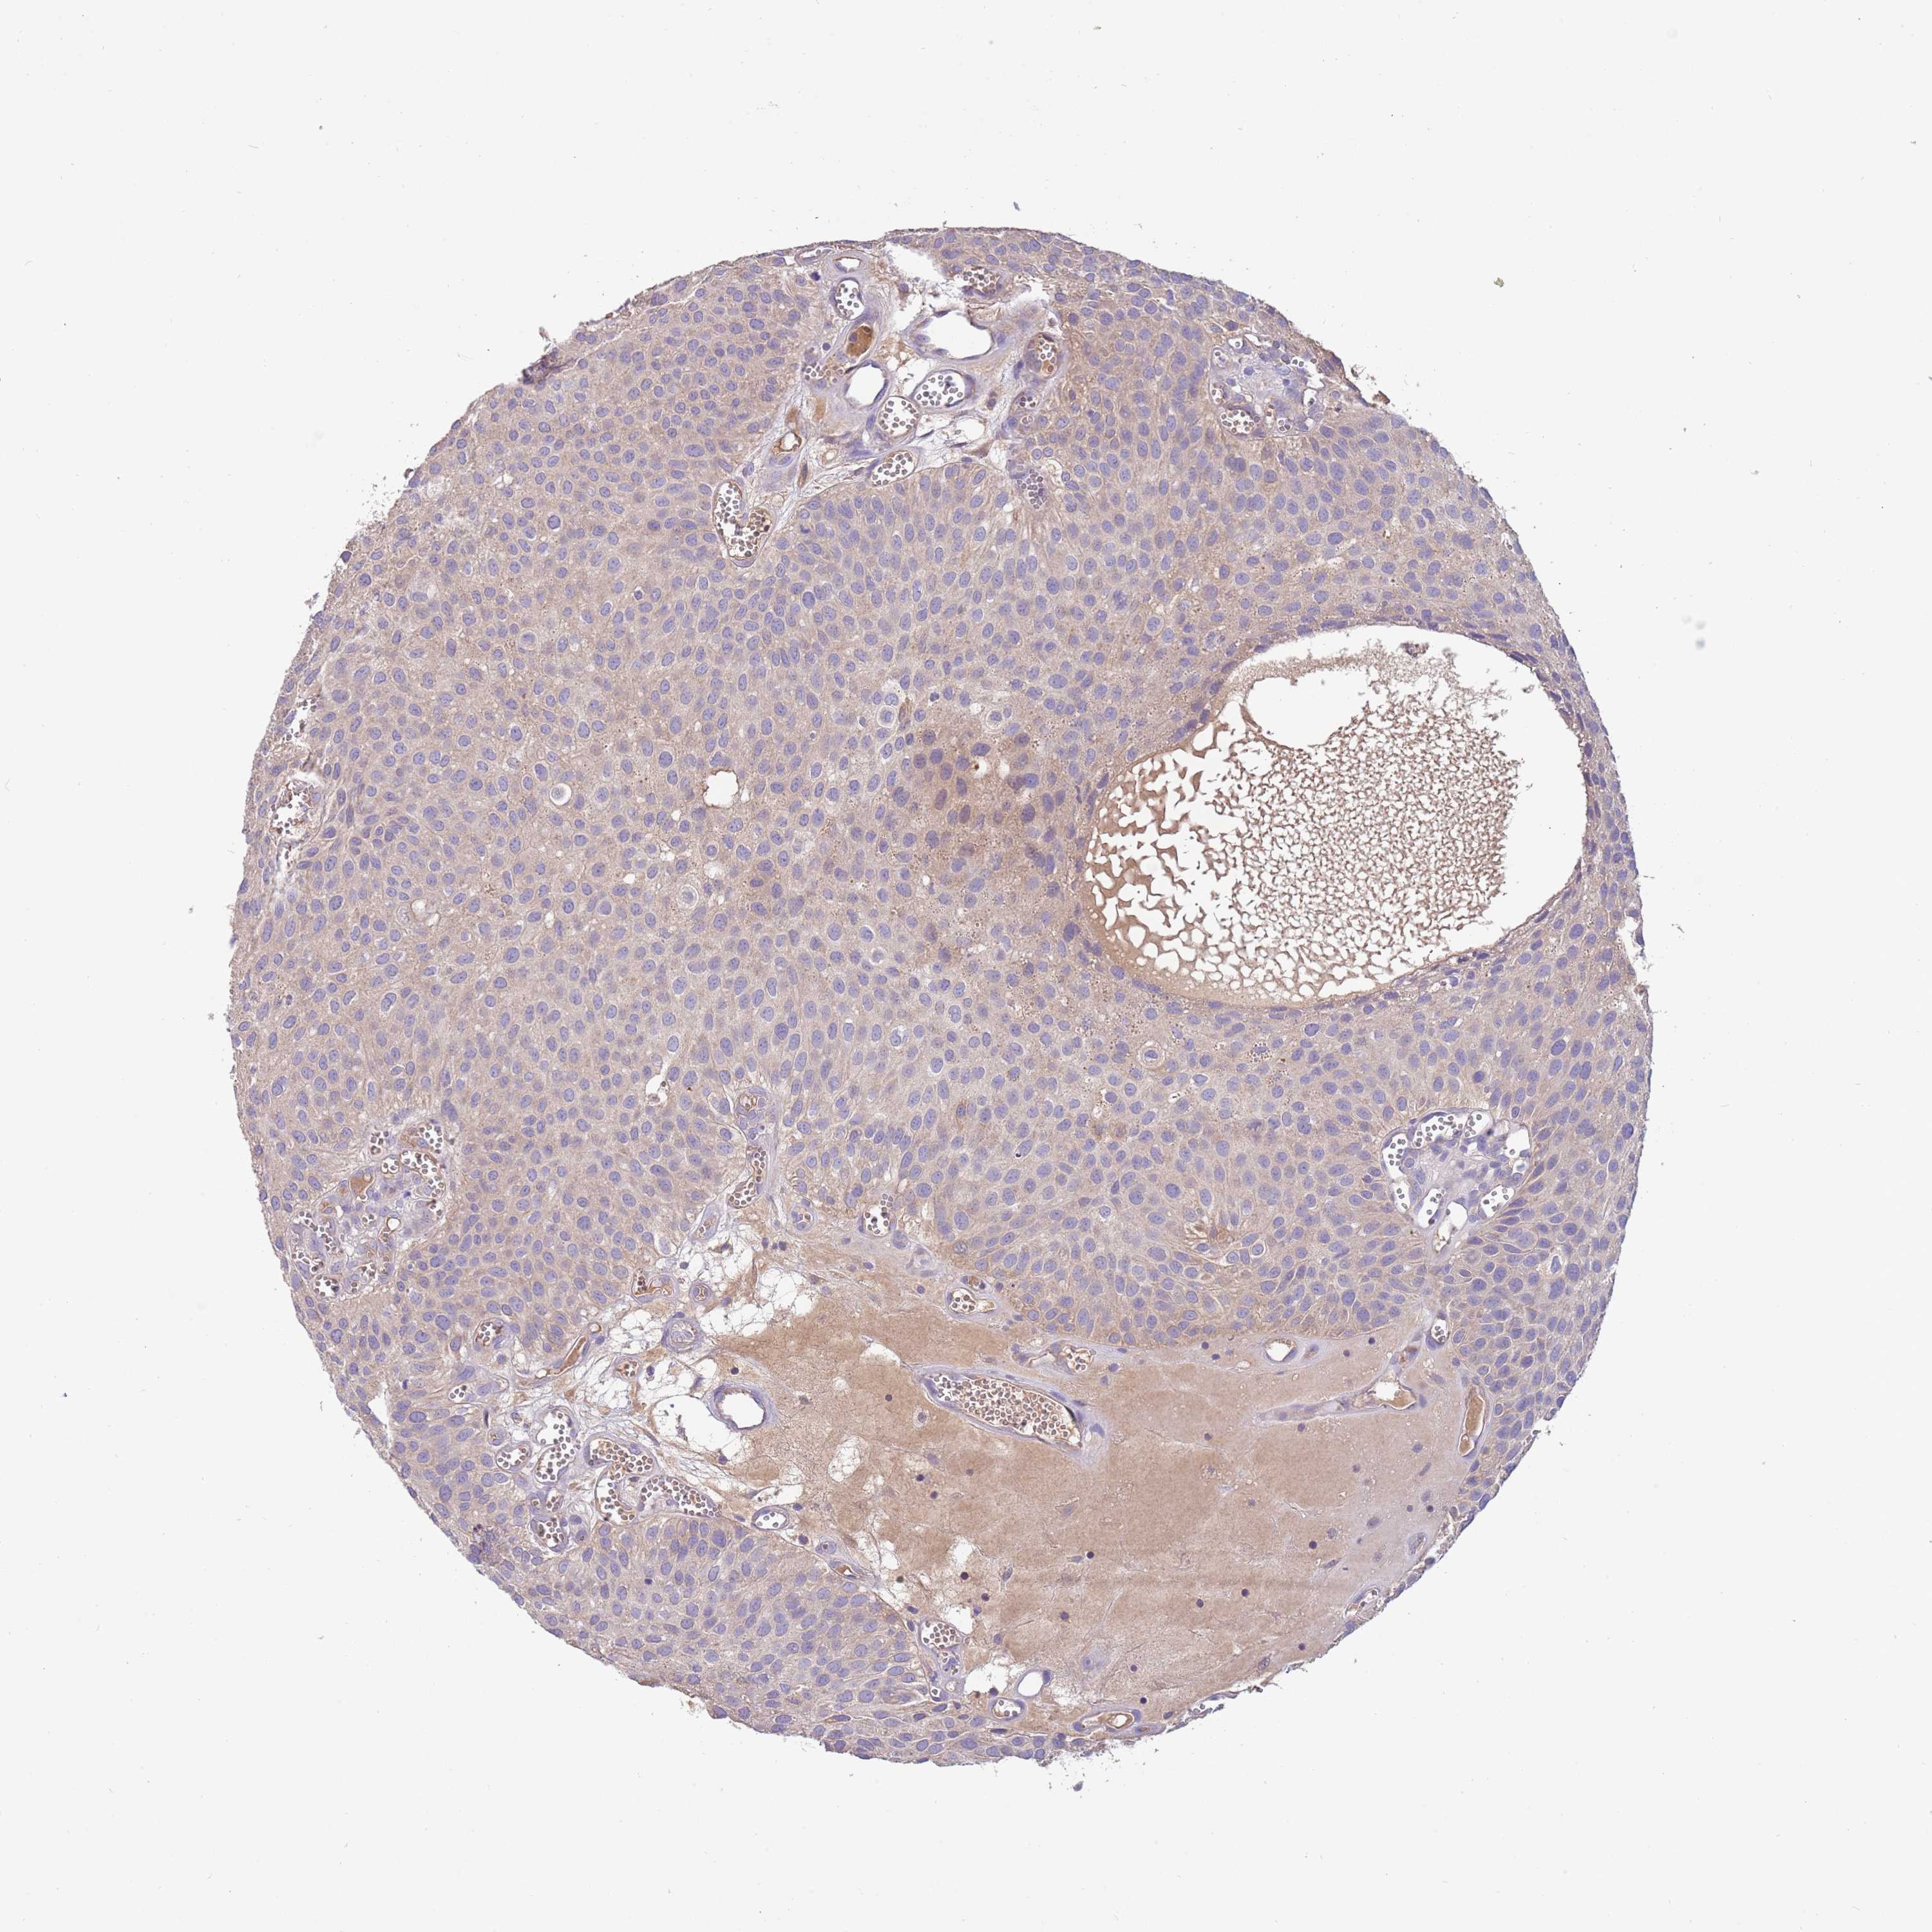

UROTHELIAL CANCER - Protein expressioni

A mouse-over function shows sample information and annotation data. Click on an image to view it in a full screen mode. Samples can be filtered based on level of antibody staining by selecting one or several of the following categories: high, medium, low and not detected. The assay and annotation is described here.

Note that samples used for immunohistochemistry by the Human Protein Atlas do not correspond to samples in the TCGA dataset.

Antibody stainingi

Antibody staining in the annotated cell types in the current human tissue is reported as not detected, low, medium, or high, based on conventional immunohistochemistry profiling in selected tissues. This score is based on the combination of the staining intensity and fraction of stained cells.

Each image is clickable and will lead to virtual microscopy that enables deeper exploration of all samples and also displays staining intensity scores, fraction scores and subcellular localization as well as patient and tissue information for each sample.

Antibody HPA021281

Staining

High

Medium

Low

Not detected

Intensity

Strong

Moderate

Weak

Negative

Quantity

>75%

75%-25%

<25%

None

Location

Nuclear

Cytoplasmic/membranous

Cytoplasmic/membranous,nuclear

Urothelial carcinoma, Low grade

Urothelial carcinoma, High grade

Urothelial carcinoma, NOS